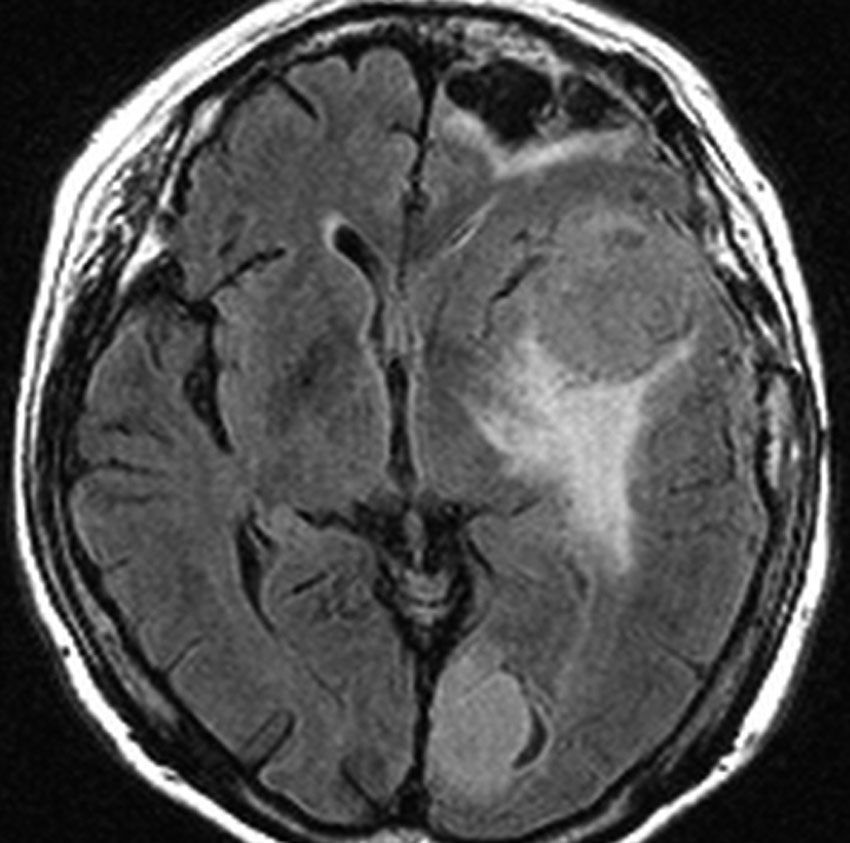

片側髄膜腫症 unilateral meningiomatosis

50歳ころから15年間に3回の開頭手術を受けている患者さんです。parasagittal, falx, convexityなど6個の髄膜腫がすでに摘出されています。左側だけ,テント上だけに髄膜腫が20個くらい多発していました。これらはグレード1で,anaplastic meningiomaの転移ではありません。

やがて蝶形骨縁の髄膜腫の増大速度が早まりatypical meningiomaとなりました。MIB-1 index が10%の高値でした。病理学的にも,psamomatous meningiomaなど様々な種類の髄膜腫が多発しています。

初発時から多発性髄膜腫であり,最初の手術で左側テント上の硬膜を広範囲に摘出しておくべきでした。このような病態は若年者でもみられることがあり,胎生期の硬膜の原基になる細胞にmutationが生じたとしか考えづらいものです。